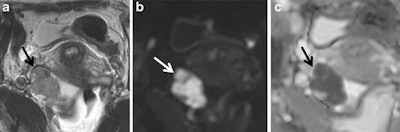

Ovarian carcinoma confined to the right ovary (arrow) displaying intermediate signal intensity on T2-weighted imaging and restricted diffusion characterized by high signal intensity on the high b-value (b = 1,200) image and loss of signal on apparent diffusion coefficient. All images courtesy of Dr. Rosemarie Forstner."The clinical impact of defining whether an indeterminate mass is benign or malignant is enormous," they wrote. "Women believed to have ovarian cancer may require radical cytoreductive surgery by a specialist surgeon in gynecological oncology. Furthermore, women with suspected malignancy may require transfer to a specialist institution. Conversely, benign adnexal masses may either be managed conservatively or undergo simple resection by a general gynecologist."